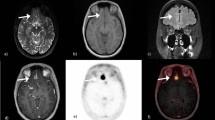

The commonly-used Gd-DOTA contrast agent to detect tumors was then intravenously injected in the mice. As shown in Fig. 6b, Gd-DOTA leaked into some metastases (inducing a 36% drop of their T1 values, p < 0.01) as demonstrated by the hypo-intense signal on the acquired 3D T1 maps post injection. Comparably with MEMRI obtained right after the injection of MnCl2, only those metastases with a leaky vasculature could internalize Mn2+ ions. Metastases in Fig. 6c,d did not internalize either Mn2+ or Gd-DOTA. It is important to note that there was no correlation between the T1 values of the metastases before MnCl2 injection and the permeability of the blood-tumor barrier (BTB). Indeed, two metastases with similar T1 before MnCl2 injection (1252 ms and 1282 ms) belonged to the High and Null populations after injection, respectively.

3D T1 maps of mouse brains with metastases, immediately after the injection of MnCl2 or Gd-DOTA.

The metastases that internalized Mn2+ ions (arrow in a) were the ones that had a leaky vasculature (as shown by the short T1 value after Gd-DOTA injection in b). On the contrary, metastases with intact BTB didn’t internalize Mn2+ or Gd-DOTA (arrows in c and d). The scale bar represents 2 mm.